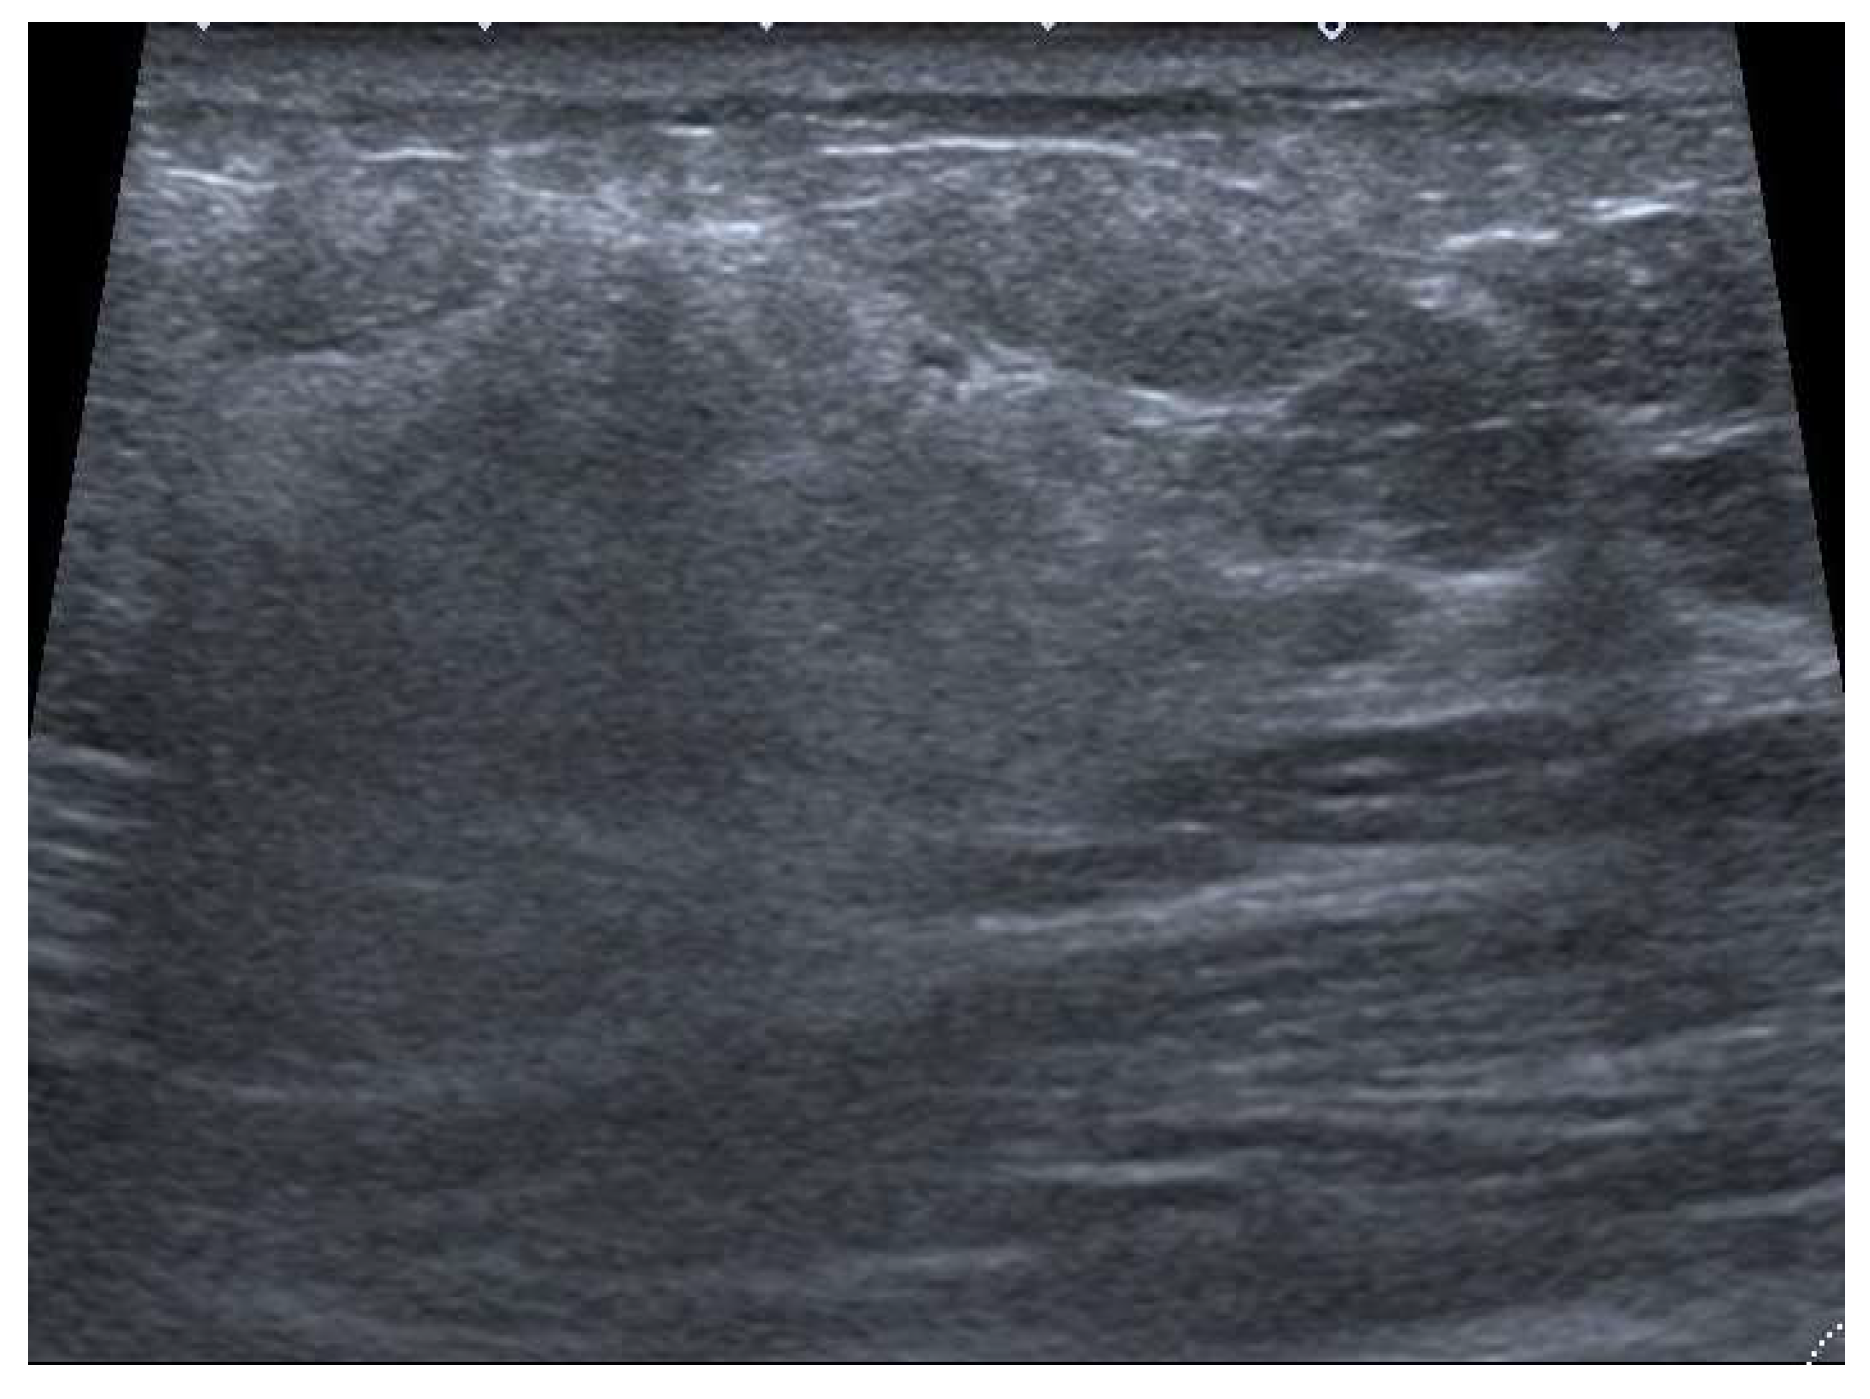

4.2. Ultrasound